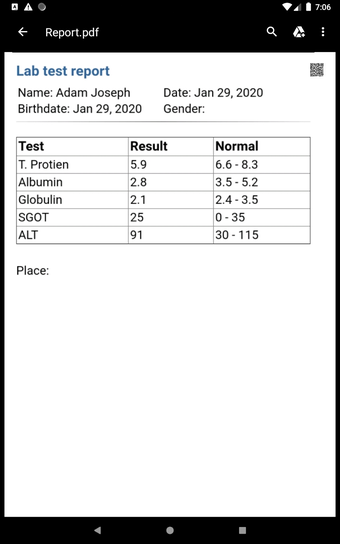

The Android Medical Records App by MedClin is a free medical records tracker app that allows users to store anamnesis, patient records, patient history, and health information. It is easy to use and provides numerous features such as username and password authentication, exporting medical data to Excel Sheet, and the ability to attach medical documents of any type. The app also has a smart search feature that allows users to search for patient information by name or ID, and even capture a photo for their profile.

In addition, the app has a blood pressure module that measures systolic, diastolic, and pulse, and allows users to export blood pressure reports to either PDF or graphs. The app also has a blood glucose (sugar) module that records blood sugar values and allows users to export blood glucose reports to either PDF or graphs. Users can also send blood pressure and blood sugar reports to their doctor. The app is compatible with multiple screens, including phones and tablets, and works on Chromebook systems. Overall, the Android Medical Records App is a great tool for patients and physicians alike for managing patient information and medical records.